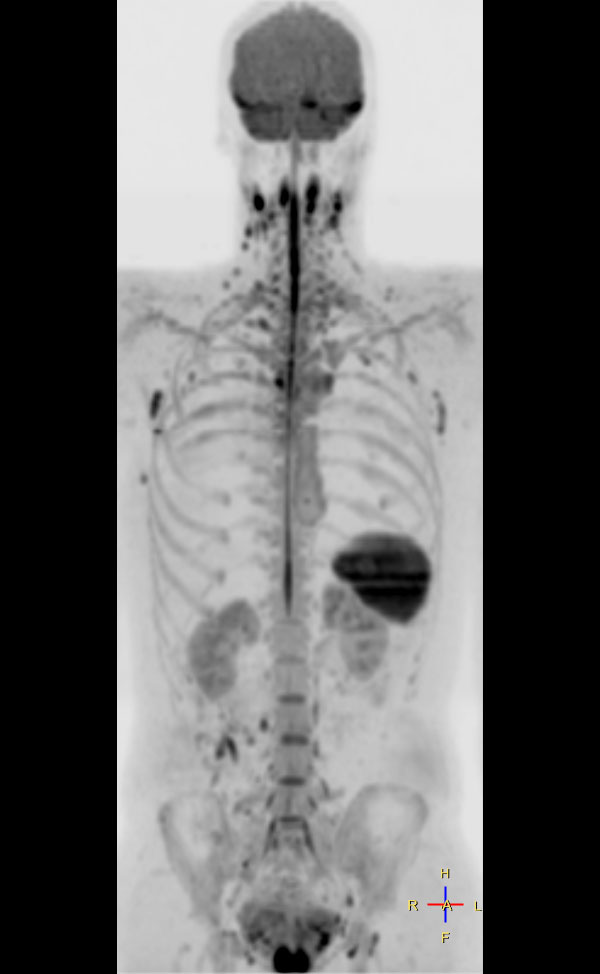

Total Body Imaging

Whole Body imaging